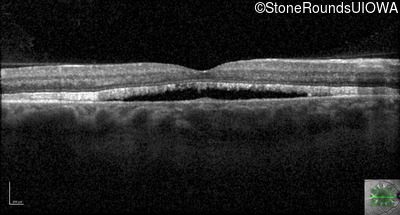

Optical Coherence Tomography - Left - 20/20

Exemplar / OCT Stack

OCT Stack